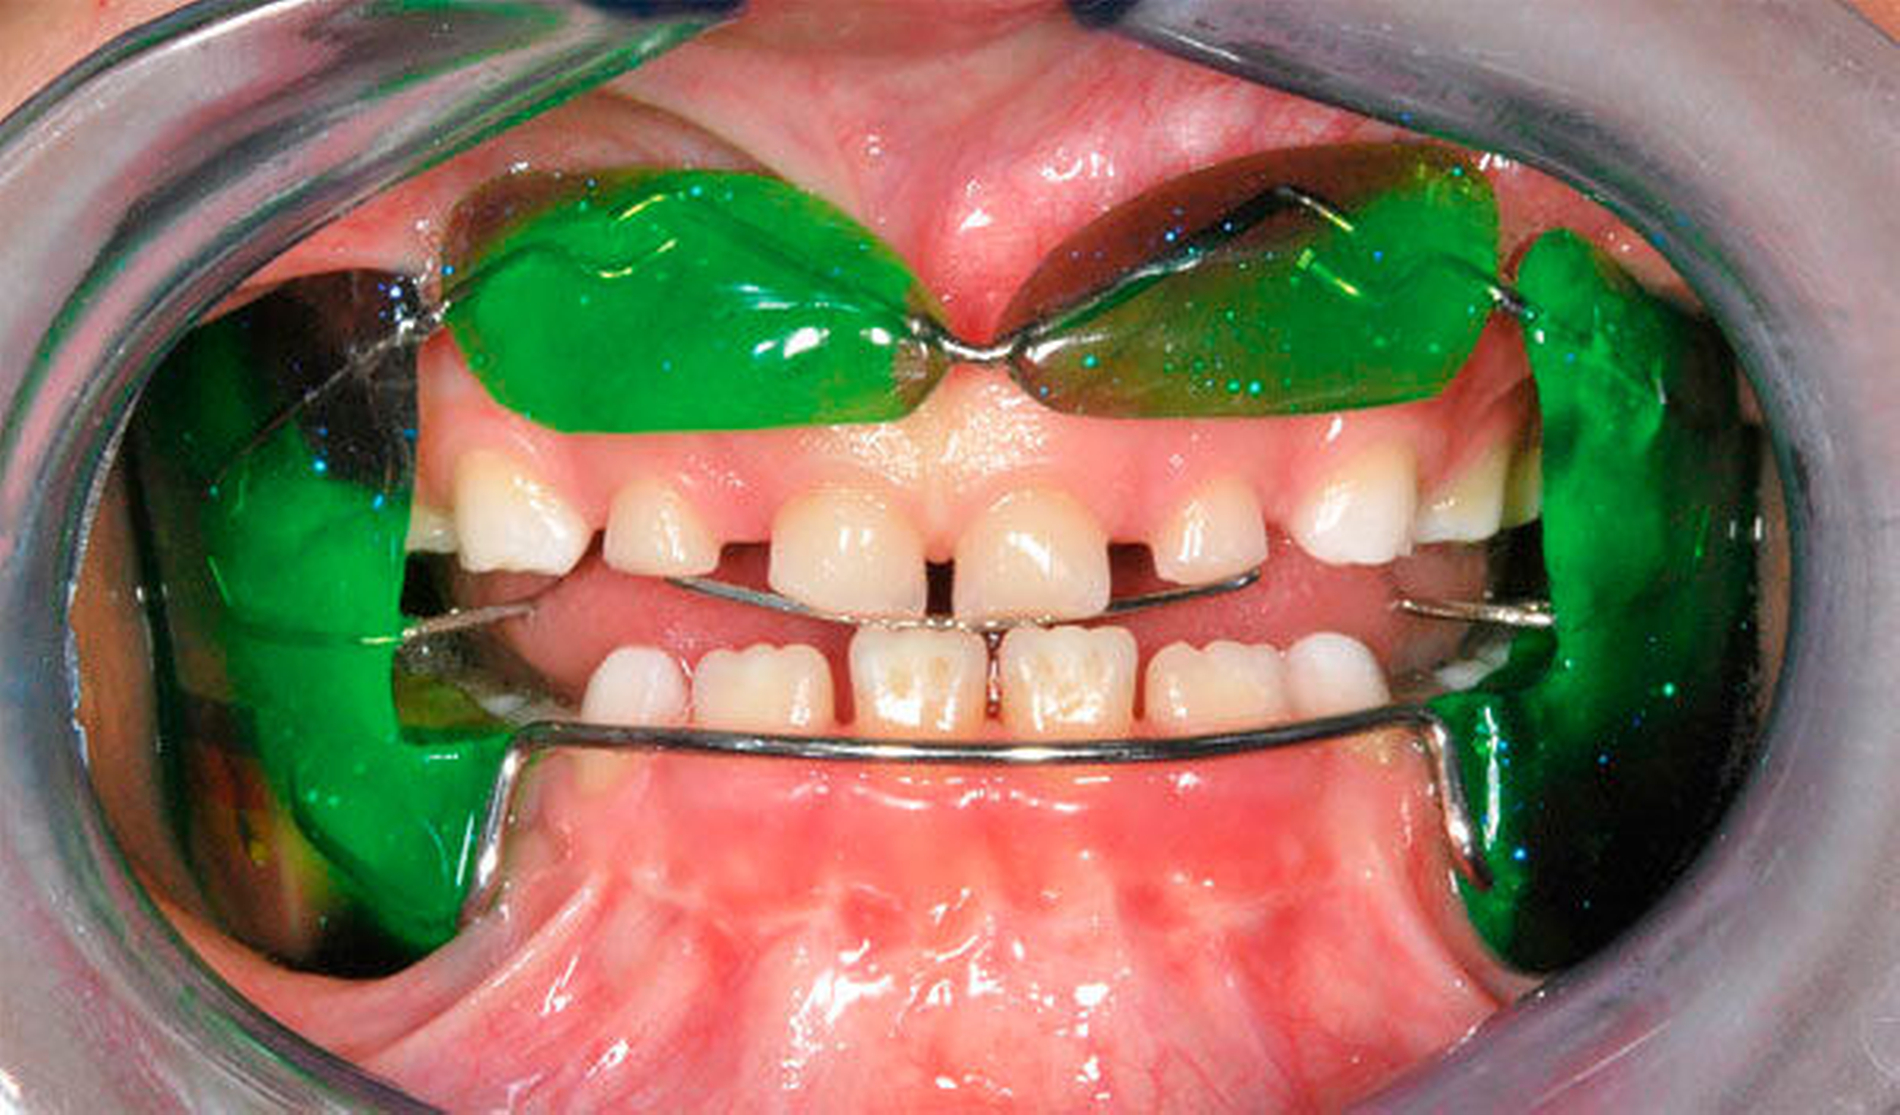

Besonders wichtig ist aus zahnärztlich-kieferorthopädischer Sicht die Beurteilung der lateralen Okklusionsverhältnisse [Kahl-Nieke, 2015]. Der unilaterale Kreuzbiss kommt ungefähr viermal häufiger vor als der bilaterale [Schopf, 2003]. Bei 80 Prozent der Kinder mit einseitigem Kreuzbiss tritt eine funktionelle Unterkieferabweichung auf [Kurol, 1992] und die Unterkiefermitte verschiebt sich dabei zur Kreuzbissseite [Santos Pinto, 2001] bei gleichzeitig asymmetrischer Kondylenposition. Diese reflektorische Einnahme der Kreuzbissstellung vergrößert die Anzahl der Okklusionskontakte, mit der Gefahr, dass nach kurzer Zeit diese transversale Fehlstellung des Unterkiefers neuromuskulär fixiert wird. Bei Belassen des Kreuzbisses kann eine skelettale Manifestation der Asymmetrie und eine dauerhafte Abweichung der Kinnmitte von der Gesichtsmitte resultieren [Hesse, 1997; O`byrn, 1995]. Erfolgt keine frühzeitige Therapie, besteht zudem die Gefahr einer Wachstumshemmung im Bereich der im Kreuzbiss „eingefangenen“ Oberkieferseite. Eine kieferorthopädische Frühbehandlung scheint präventiv gegen eine skelettale Adaptation und gegen eine Persistenz des Kreuzbisses in die permanente Dentition zu wirken [Harrison, 2001]. Das Überstellen des lateralen Kreuzbisses durch transversale Weitung des Oberkiefers kann beispielsweise mittels forcierter Gaumennahterweiterung [Köbel, 2017] erfolgen und wirkt sich neben einer Verbesserung der respiratorischen Situation günstig auf die Beseitigung skelettaler und dentoalveolärer Asymmetrien aus [Hesse, 1997; Santos Pinto, 2001] (Abbildung 3).